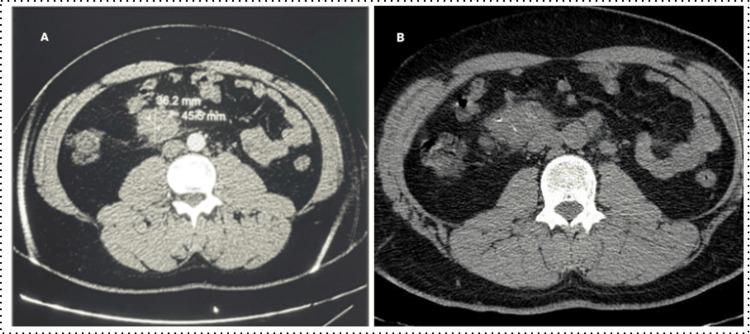

Acute myeloid leukemia (AML) is a hematologic malignancy that often requires hematopoietic stem cell (HSC) allografting after relapse. Tuberculosis (TB) remains a significant concern in regions where it is endemic, posing a challenge in the management of these patients. A 38-year-old male with AML, who achieved complete remission after induction chemotherapy and three consolidation courses, relapsed one year later with additional chromosomal abnormalities. He received FLAG-Ida salvage chemotherapy and achieved both hematological and cytogenetic remission. During the pre-allograft check-up, an abdominal ultrasound revealed mesenteric adenopathies, and biopsy confirmed tuberculous adenitis. Given the urgency of HSC transplantation, the patient initiated anti-bacillary therapy (ERIP K4 capsules per day for three weeks) before starting his FB4 conditioning regimen. The therapy was continued during the transplant process. The patient completed six months of anti-bacillary treatment, with no TB reactivation observed at the latest follow-up. This case highlights the critical need for screening both donors and recipients for latent and active TB infection in endemic regions. Current literature supports the importance of pre-transplant TB screening and tailored management to address the complexities of TB treatment in stem cell transplantation, particularly in TB-endemic areas.

急性髓系白血病(AML)是一种血液系统恶性肿瘤,复发后常需进行造血干细胞(HSC)同种异体移植。在结核病(TB)流行地区,结核病仍然是一个重大问题,给这些患者的管理带来了挑战。一名38岁的AML男性患者,在诱导化疗和三个巩固疗程后达到完全缓解,一年后复发并伴有额外的染色体异常。他接受了FLAG-Ida挽救化疗,实现了血液学和细胞遗传学缓解。在移植前检查期间,腹部超声显示肠系膜淋巴结肿大,活检证实为结核性腺炎。鉴于HSC移植的紧迫性,患者在开始FB4预处理方案之前启动了抗结核治疗(每天服用ERIP K4胶囊,持续三周)。治疗在移植过程中持续进行。患者完成了六个月的抗结核治疗,在最近的随访中未观察到结核病复发。该病例突出了在流行地区对供体和受体进行潜伏性和活动性结核感染筛查的迫切需求。当前文献支持移植前结核筛查和定制管理的重要性,以应对干细胞移植中结核治疗的复杂性,特别是在结核病流行地区。